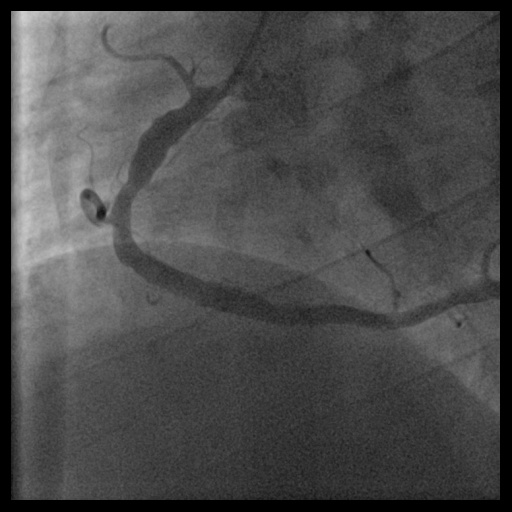

Relevant Catheterization Findings

During this emergency catheterization, the right radial artery was accessed using a 20-gauge needle. A 6 Fr in 5 Glidesheath Slender® (Terumo Corp., Tokyo, Japan) was inserted. Coronary angiography was performed using Terumo 5 Fr Judkins catheters, revealing in-stent total occlusion of the RCA and patent left coronary artery (LCA).